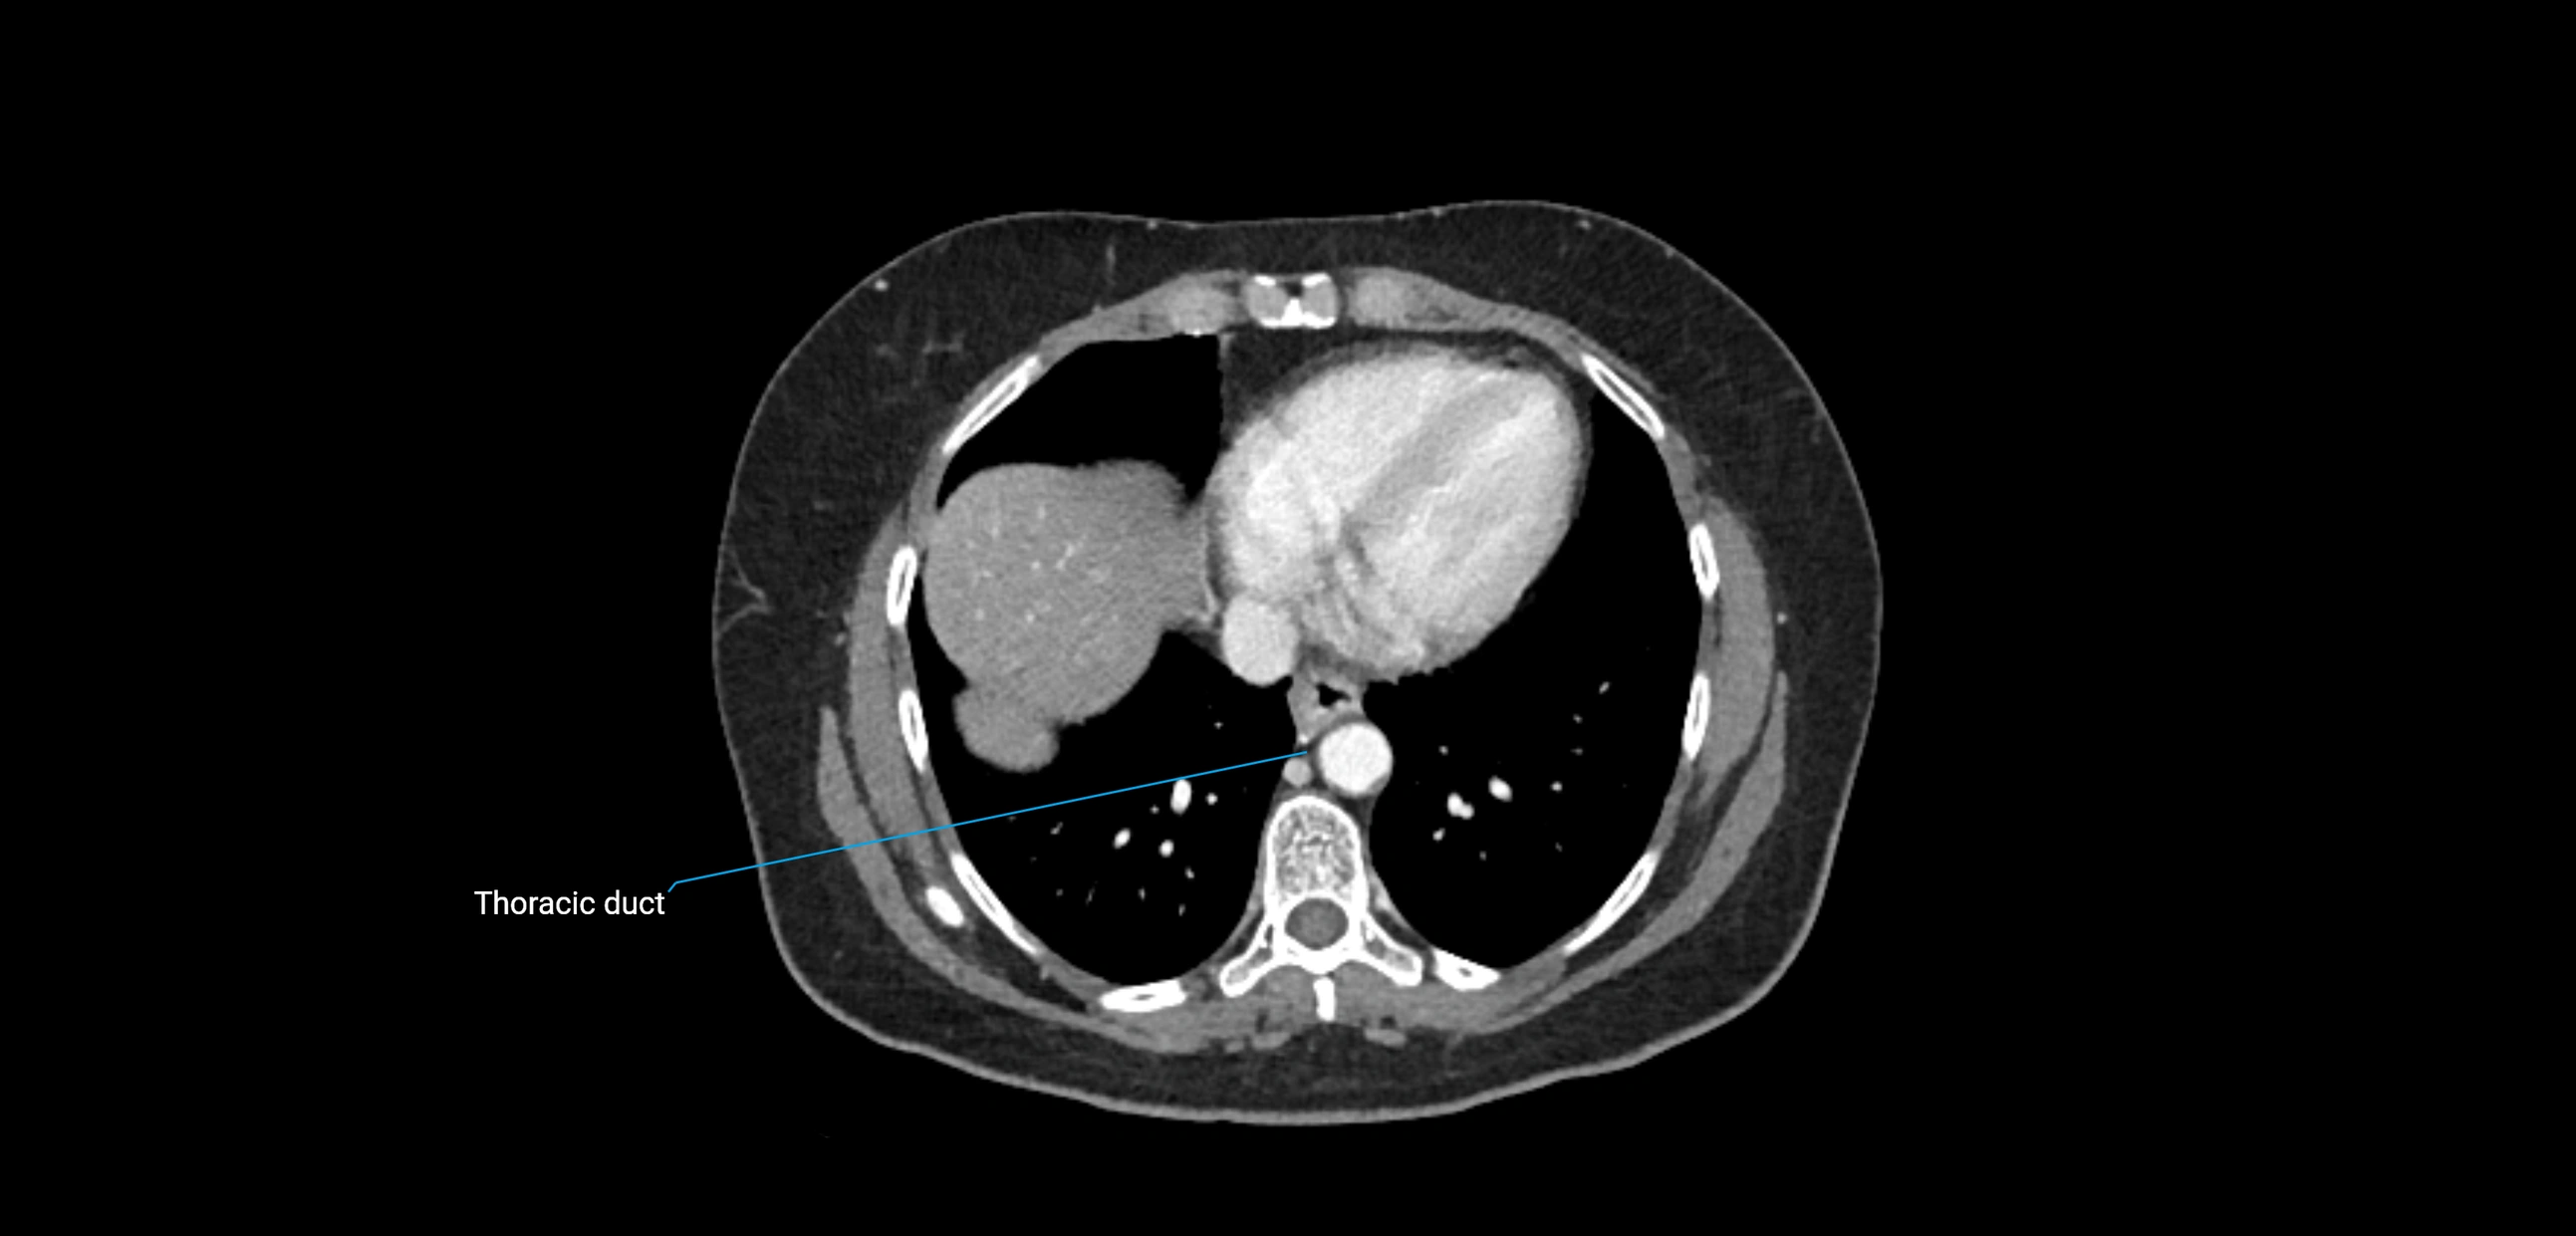

These nodes receive lymph from a wide range of abdominal and pelvic structures. Specifically, they drain lymph from the kidneys, suprarenal glands, gonads (testes/ovaries), uterus, uterine tubes, and pelvic organs, before converging into the lumbar lymphatic trunks, which terminate in the cisterna chyli → thoracic duct.

• Provide a major pathway to the cisterna chyli and thoracic duct